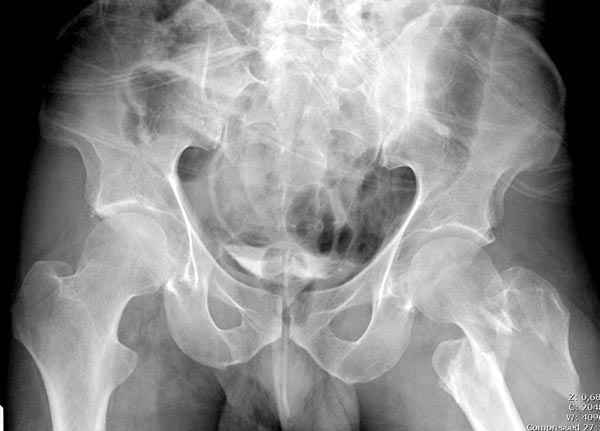

Не солидно экономить на пленке, это не делает чести презентации. Такие ограниченные нестандартные снимки приводят к тактическим ошибкам.

Предугадать распространение линий перелома при чрезвертельных и оскольчатых переломах трудно, поэтому для принятия правильного решения рекомендуется Компьютерно Томографические исследование.

При отсутствии КТ, снимок на вытяжении поможет увидеть общую картину расположения отломков, особенно потенциальные места введения импланта. Риск раскола в этом случае огромный, поэтому больной должен быть дообследован.

Здесь пара похожих случаев.